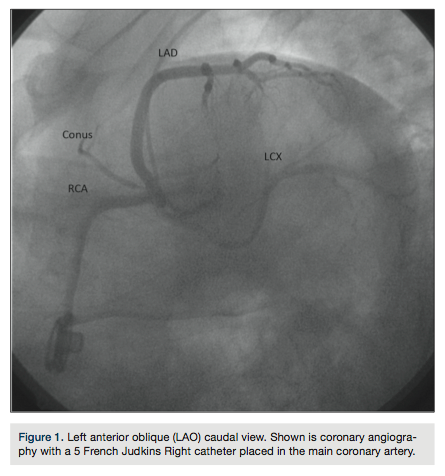

abnormal electrocardiogram (ECG) was referred for further evaluation. Review of his ECG showed 2-mm ST elevation in leads V2 and V3, and 1-mm ST elevation in leads V4-V6. Transthoracic echocardiography showed only mild global left ventricular (LV) hypokinesis. Subsequent coronary angiography (Figure 1) revealed a single common coronary artery (SCA) arising from the right coronary cusp with no significant obstructive disease and a dominant right coronary artery (RCA) that wrapped around the left ventricular apex. Computed tomography coronary angiography (Figures 2-5) confirmed the right coronary cusp origin. The left anterior

descending coronary artery (LAD) was shown to course anterior to the pulmonary artery. The left circumflex and RCA followed a relatively normal course; the RCA was confirmed to be large and to cover an extensive part of the inferior and apical left ventricular walls.